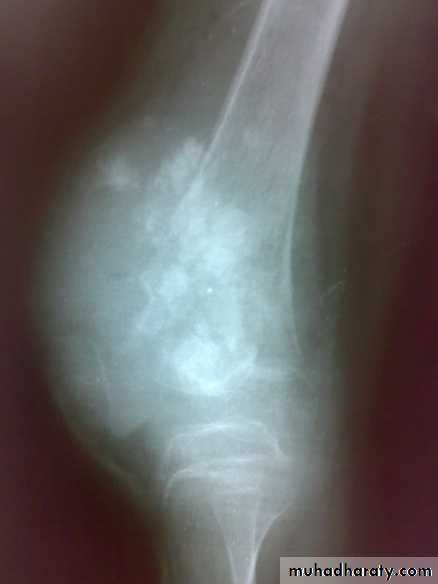

X-ray show eccentric osteolytic lesion in the end of long bone ,subchondral, trabeculated (soap bubble appearance). The cortex is thin, expanded or even perforated.